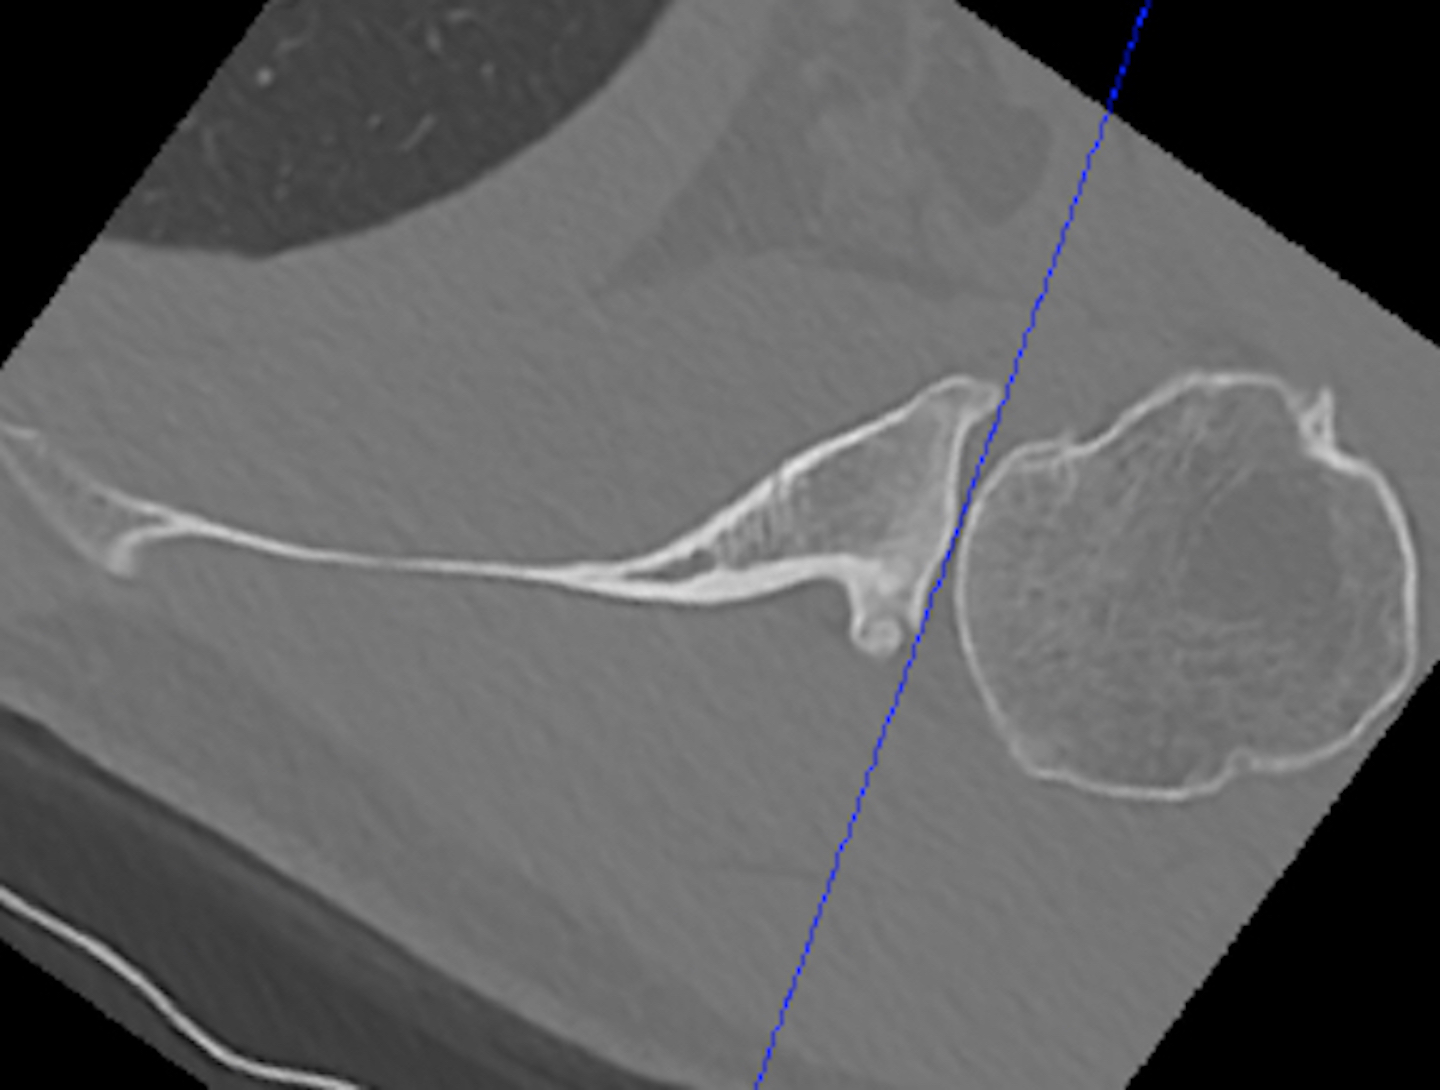

2. Include scapula

Chalmers et al. J Should Elbow Surg 2017

- 14 B2 glenoids

- glenoid version measurement accurate if > 50% of the scapula width included

3. Measurement techniques

a. Friedman method

- tip of the medial border of the scapula to the midpoint of the glenoid fossa

b. Scapula body method

- intersection of the scapula body axis and the glenoid surface

- 3o difference in measurement of glenoid version between the two

- excellent reliability for both measurement techniques

c. Glenoid vault method

- tip of scapula vault to centre of glenoid